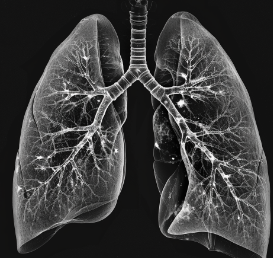

3. 폐결절 발견 방법: 흉부 X-ray, CT 검사

| 요약 | 대개 무증상, 흉부 방사선 촬영과 CT 검사로 발견 |

| 방법 | 흉부 X선 촬영, 흉부 CT 촬영 |

| 특징 | 과거 검사 결과와 비교하여 크기 변화 확인 |

폐결절은 대개 무증상이며, 대부분 흉부 방사선 촬영을 통해 발견됩니다. 최근에는 국가암검진 저선량 CT 검사에서도 폐결절이 발견되기도 합니다. 이는 조기 발견의 중요성을 강조하는 대목입니다.

폐결절의 진단은 주로 흉부 X선 촬영과 흉부 CT 촬영을 통해 이루어집니다. 흉부 X선 검사에서는 과거 검사 결과와 비교하여 결절의 크기 변화를 확인합니다. 이를 통해 결절의 성장 속도와 성격을 파악할 수 있습니다.

정확한 진단을 위해서는 여러 번의 검사가 필요할 수 있으며, 특히 결절의 크기와 모양이 변화하는지를 주의 깊게 관찰해야 합니다.